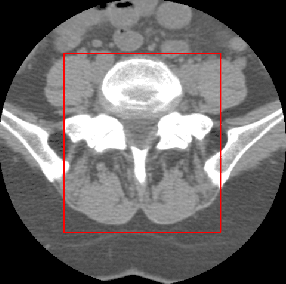

Abstract:There has been a significant increase from 2010 to 2016 in the number of people suffering from spine problems. The automatic image segmentation of the spine obtained from a computed tomography (CT) image is important for diagnosing spine conditions and for performing surgery with computer-assisted surgery systems. The spine has a complex anatomy that consists of 33 vertebrae, 23 intervertebral disks, the spinal cord, and connecting ribs. As a result, the spinal surgeon is faced with the challenge of needing a robust algorithm to segment and create a model of the spine. In this study, we developed an automatic segmentation method to segment the spine, and we compared our segmentation results with reference segmentations obtained by experts. We developed a fully automatic approach for spine segmentation from CT based on a hybrid method. This method combines the convolutional neural network (CNN) and fully convolutional network (FCN), and utilizes class redundancy as a soft constraint to greatly improve the segmentation results. The proposed method was found to significantly enhance the accuracy of the segmentation results and the system processing time. Our comparison was based on 12 measurements: the Dice coefficient (94%), Jaccard index (93%), volumetric similarity (96%), sensitivity (97%), specificity (99%), precision (over segmentation; 8.3 and under segmentation 2.6), accuracy (99%), Matthews correlation coefficient (0.93), mean surface distance (0.16 mm), Hausdorff distance (7.4 mm), and global consistency error (0.02). We experimented with CT images from 32 patients, and the experimental results demonstrated the efficiency of the proposed method.